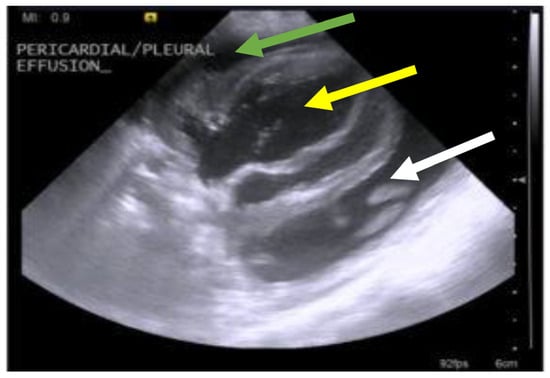

7.4. Diagnostic Imaging in FIP

7.4.1. Routine Imaging: Ultrasonographic and Radiographic Findings

7.4.2. Advanced Imaging of the CNS: MRI and CT

| Summary of Section 7: Diagnosis of FIP; Section 7.4: Diagnostic imaging in FIP: No specific ultrasonographic or radiographic findings exist for FIP. Ultrasonography (in particular) and radiography can show the presence of effusions. Pneumonia due to FIP that is occasionally reported can be associated with radiographic changes. Ultrasonography can reveal abdominal lymphadenomegaly or lymphadenopathy and/or abnormalities of the liver, spleen, intestines and/or kidneys (which can include a medullary rim sign), depending on which organs are affected. Imaging can also be of use to the direct sampling of abnormal tissues, e.g., fine-needle aspirate for cytology examination to reveal non-septic pyogranulomatous inflammation, or ultrasound-guided needle core (e.g., tru-cut) biopsies can be collected and submitted for histopathology. When a cat is showing neurological signs, the imaging of the brain by magnetic resonance imaging, if available, with contrast, can be useful to demonstrate neurological abnormalities (such as obstructive hydrocephalus, syringomyelia, foramen magnum herniation and marked contrast enhancement of the meninges, third ventricle, mesencephalic aqueduct, and brainstem). A description of computerised tomography findings in cats with neurological FIP has not been published, but MRI is likely to be more sensitive in the detection of subtle intraparenchymal lesions. Advanced imaging of the central nervous system is indicated before performing cerebrospinal fluid sampling to assess the potential risk of herniation. |